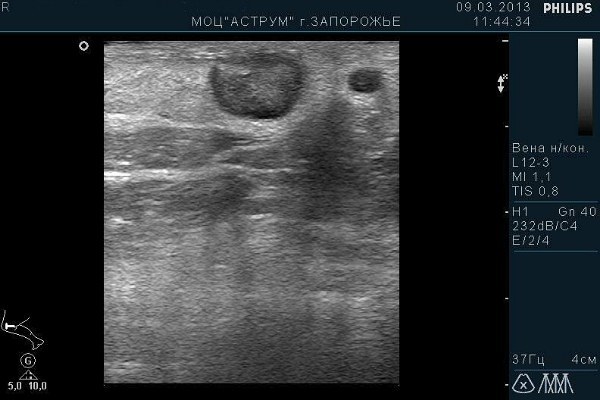

В норме вены на УЗИ имеют эхонегативный просвет, без тромбов и атеросклеротических бляшек. Стенка сосуда тонкая, без утолщений и уплотнений. В полости вены видны створки клапанов (толщина 0,9 мм), на вдохе они прижимаются к стенке вены, а на выдохе пережимают ее.

На экране прибора для УЗИ в норме просветы сосудов системы НПВ выглядят темными, а стенки – светлыми. При атеросклерозе, тромбофлебите, к примеру, видны сужения вен, деформации, преграды, уплотнения стенок. Из-за своей плотной структуры они также будут окрашены в более светлый цвет.